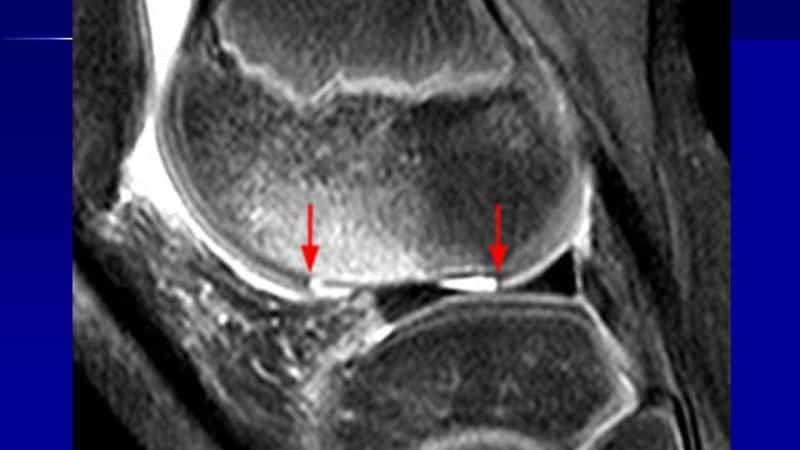

Какие анализы нужно сдать при остеоартрозе

Общий анализ мочи, биохимическое исследование крови (мочевая кислота, С-реактивный белок, фибриноген, общий белок, белковые фракции, РФ и пр.).